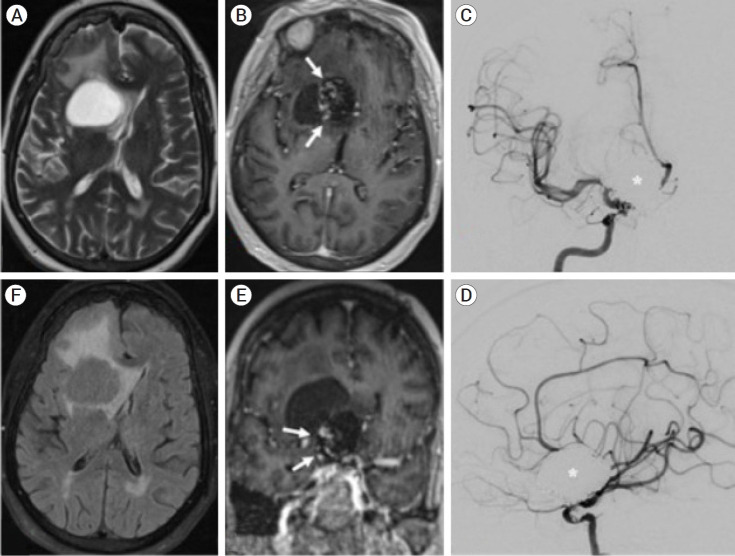

动脉瘤周围囊肿在接受治疗和未接受治疗的动脉瘤患者中都很罕见,而且人们对其了解甚少。之前的文献表明,少数肛周动脉瘤囊肿是在血管内动脉瘤治疗后 1-4 年出现的,而本最新综述表明,近一半的肛周动脉瘤囊肿是在动脉瘤夹闭术后确诊的,另一半是在治疗前与相关动脉瘤同时确诊的。64%的肛周动脉瘤囊肿经过手术减压,39%的囊肿复发,需要再次手术。我们报告了一例 71 岁女性的病例,她出现眩晕和恶心症状,在对破裂的巨大眼动脉瘤进行初次血管内卷曲治疗 20 年后,被发现有一个 3.4 厘米的肛门动脉瘤周围囊肿。该囊肿采用内窥镜穿刺术治疗,复发时再进行开腹穿刺术。该病例是文献报道的从最初动脉瘤治疗到囊肿确诊的最长潜伏期,表明即使在治疗后数十年,肛周动脉瘤囊肿的诊断仍应在鉴别诊断之列。根据病例讨论和最新文献综述,本报告重点介绍了这一具有挑战性病变的病因和治疗策略。

Perianeurysmal cysts are a rare and poorly understood finding in patients both with treated and untreated aneurysms. While the prior literature suggests that a minority of perianeurysmal cysts develop 1-4 years following endovascular aneurysm treatment, this updated review demonstrates that nearly half of perianeurysmal cysts were diagnosed following aneurysm coiling, with the other half diagnosed concurrently with an associated aneurysm prior to treatment. 64% of perianeurysmal cysts were surgically decompressed, with a 39% rate of recurrence requiring re-operation. We report a case of a 71-year-old woman who presented with vertigo and nausea and was found to have a 3.4 cm perianeurysmal cyst 20 years after initial endovascular coiling of a ruptured giant ophthalmic aneurysm. The cyst was treated with endoscopic fenestration followed by open fenestration upon recurrence. The case represents the longest latency from initial aneurysm treatment to cyst diagnosis reported in the literature and indicates that the diagnosis of perianeurysmal cyst should remain on the differential even decades after treatment. Based on a case discussion and updated literature review, this report highlights proposed etiologies of development and management strategies for a challenging lesion.